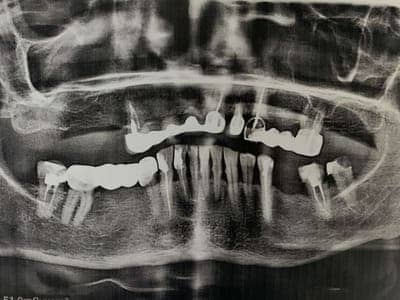

Удаление семи зубов на верхней челюсти. Одномоментная имплантация системой Neodent 6 зубов, предназначенная для немедленной нагрузки (изготовление временных коронок в день имплантации). В день имплантации сняли оттиски для временного протезирования Telio Cad. Конструкция была установлена через 2 недели после имплантации.

До

После